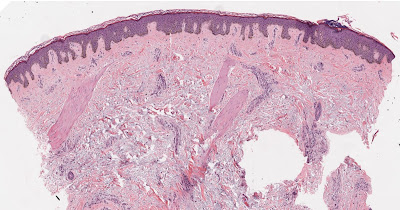

Blue material on a slide is commonly due to solar elastosis, mucin or calcium. Some bacteria and fungii may also look blue as may deposits of foreign material. If there is extensive leukocytoclasis in vasculitis the debris in the dermis can certainly look blue! Rarely a fixation artefact with hematoxylin in the dermis can look blue.

Lots of Blue cells in the dermis are seen in Spiradenoma, Cylindroma, Merkel cell carcinoma, BCC, Trichoblastoma and Lymphomas particularly B cell.